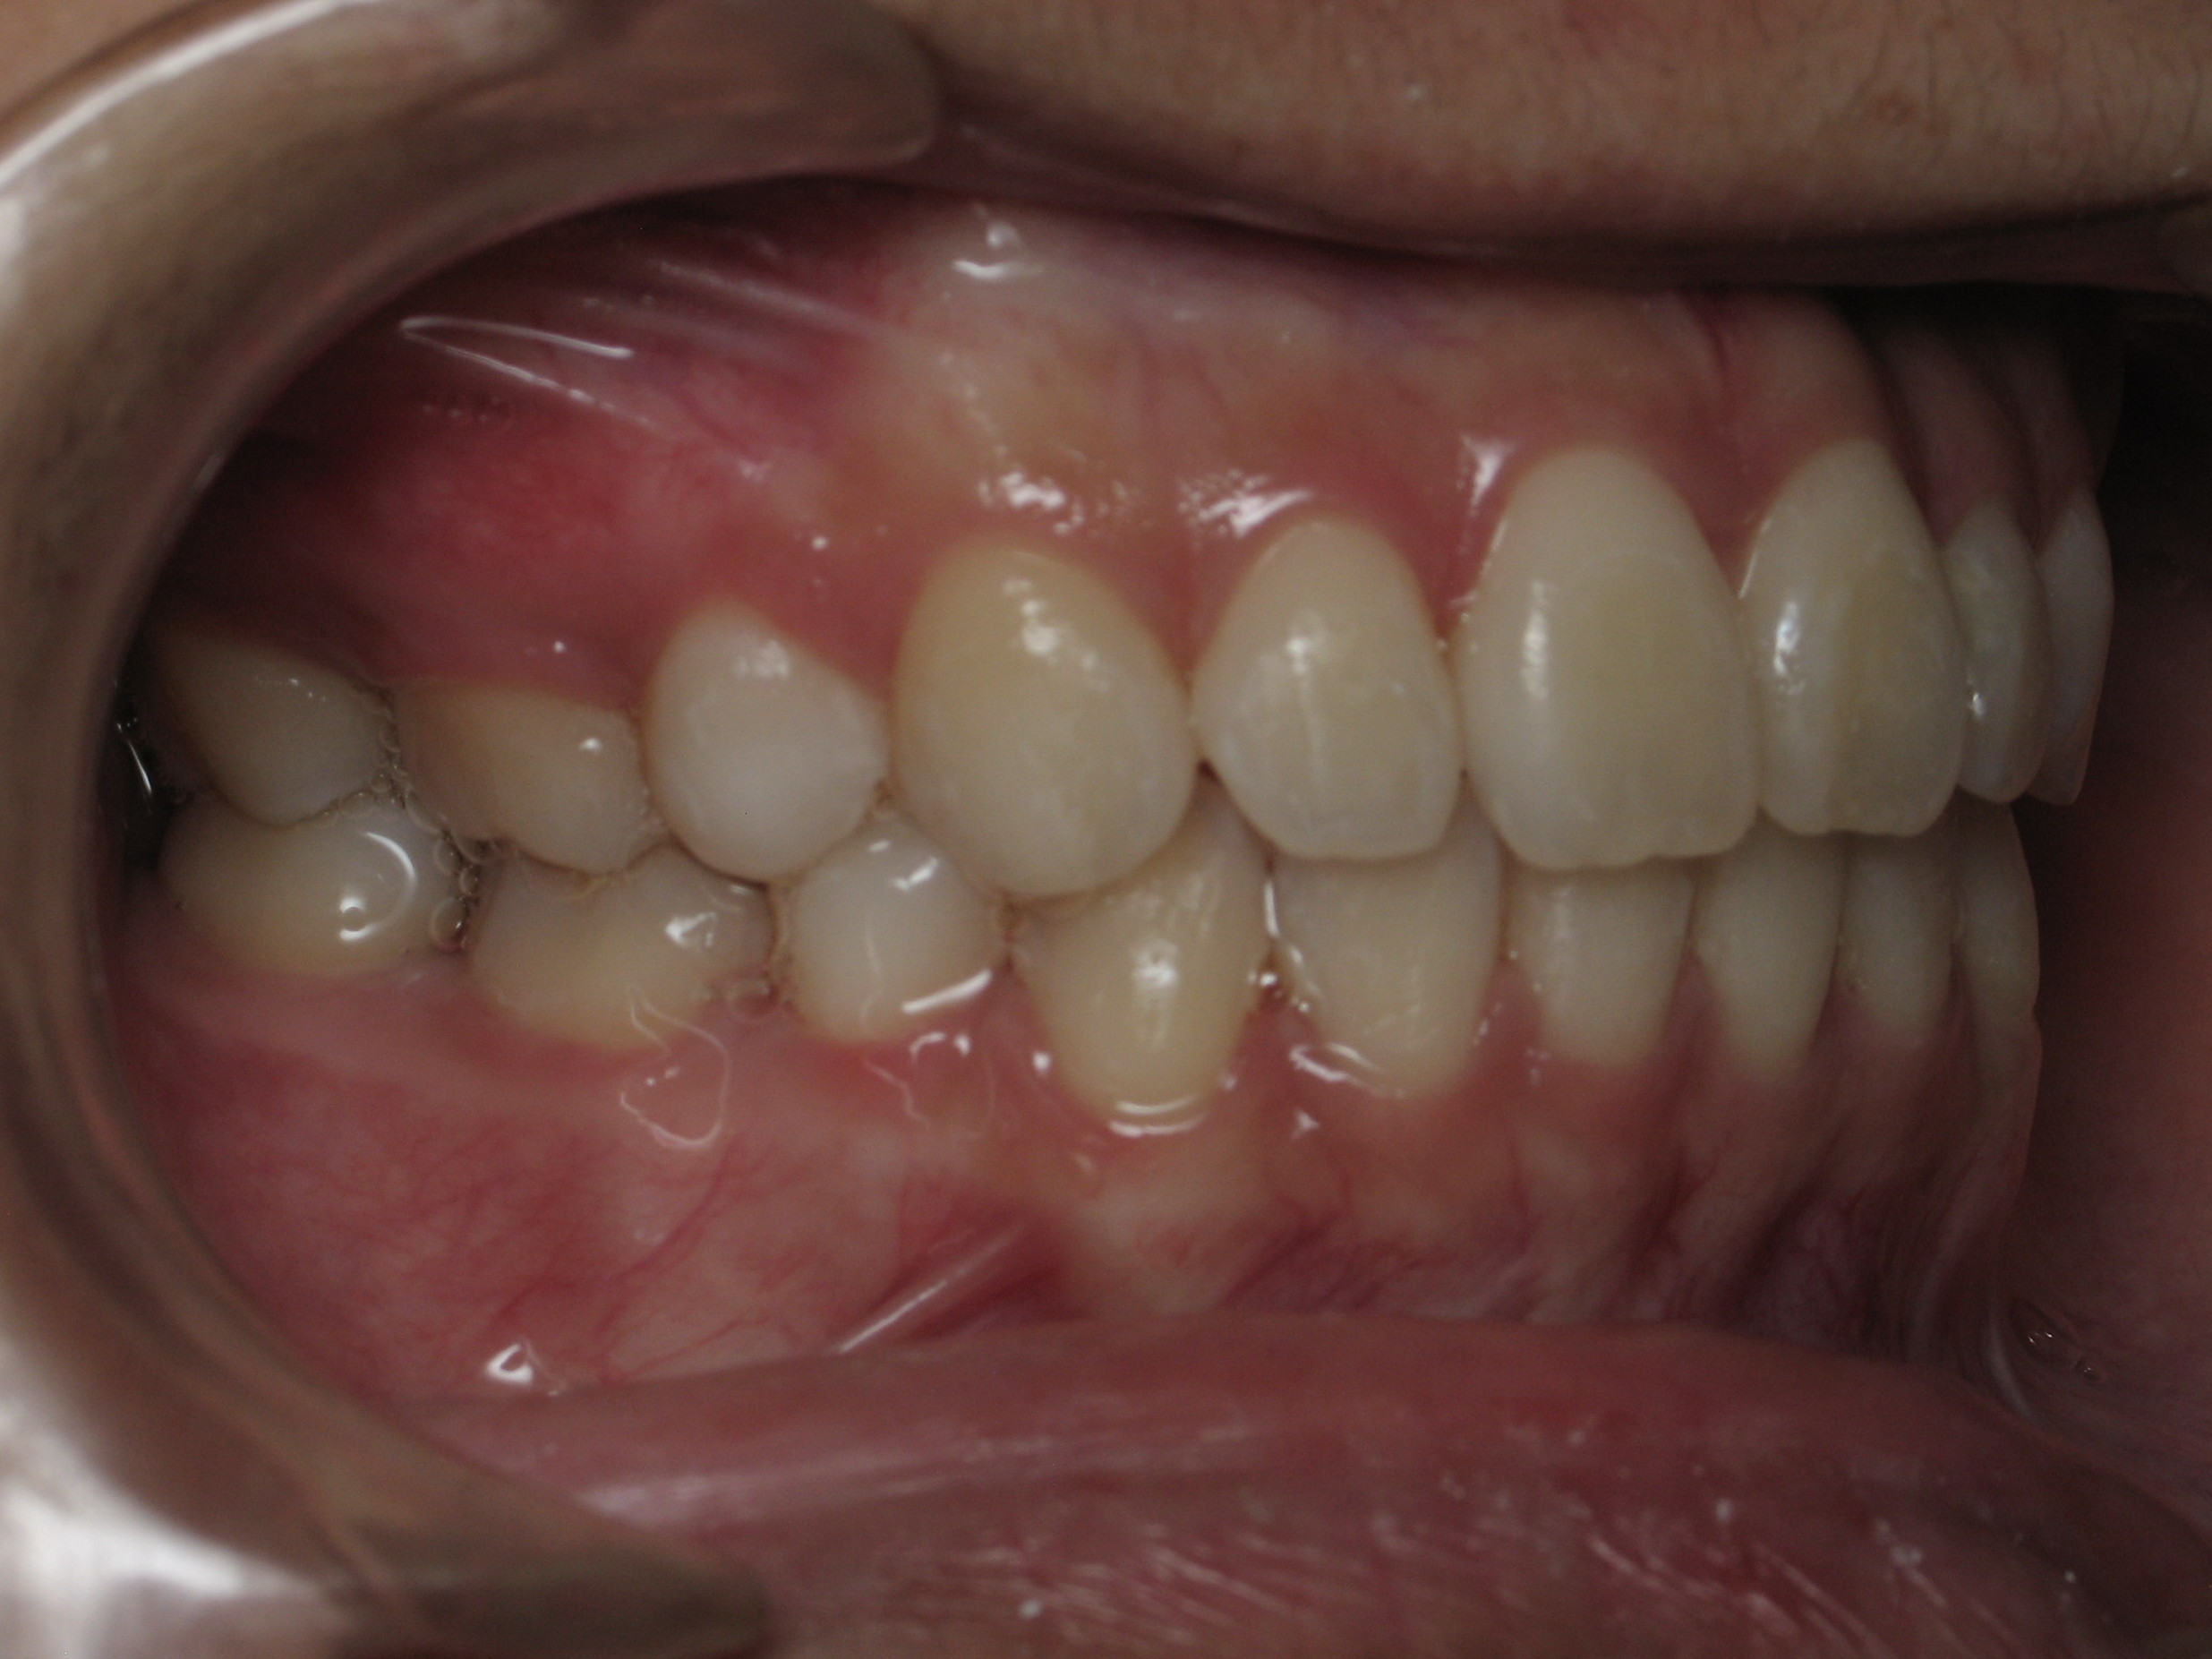

Orthodontic Treatment X-ray - After